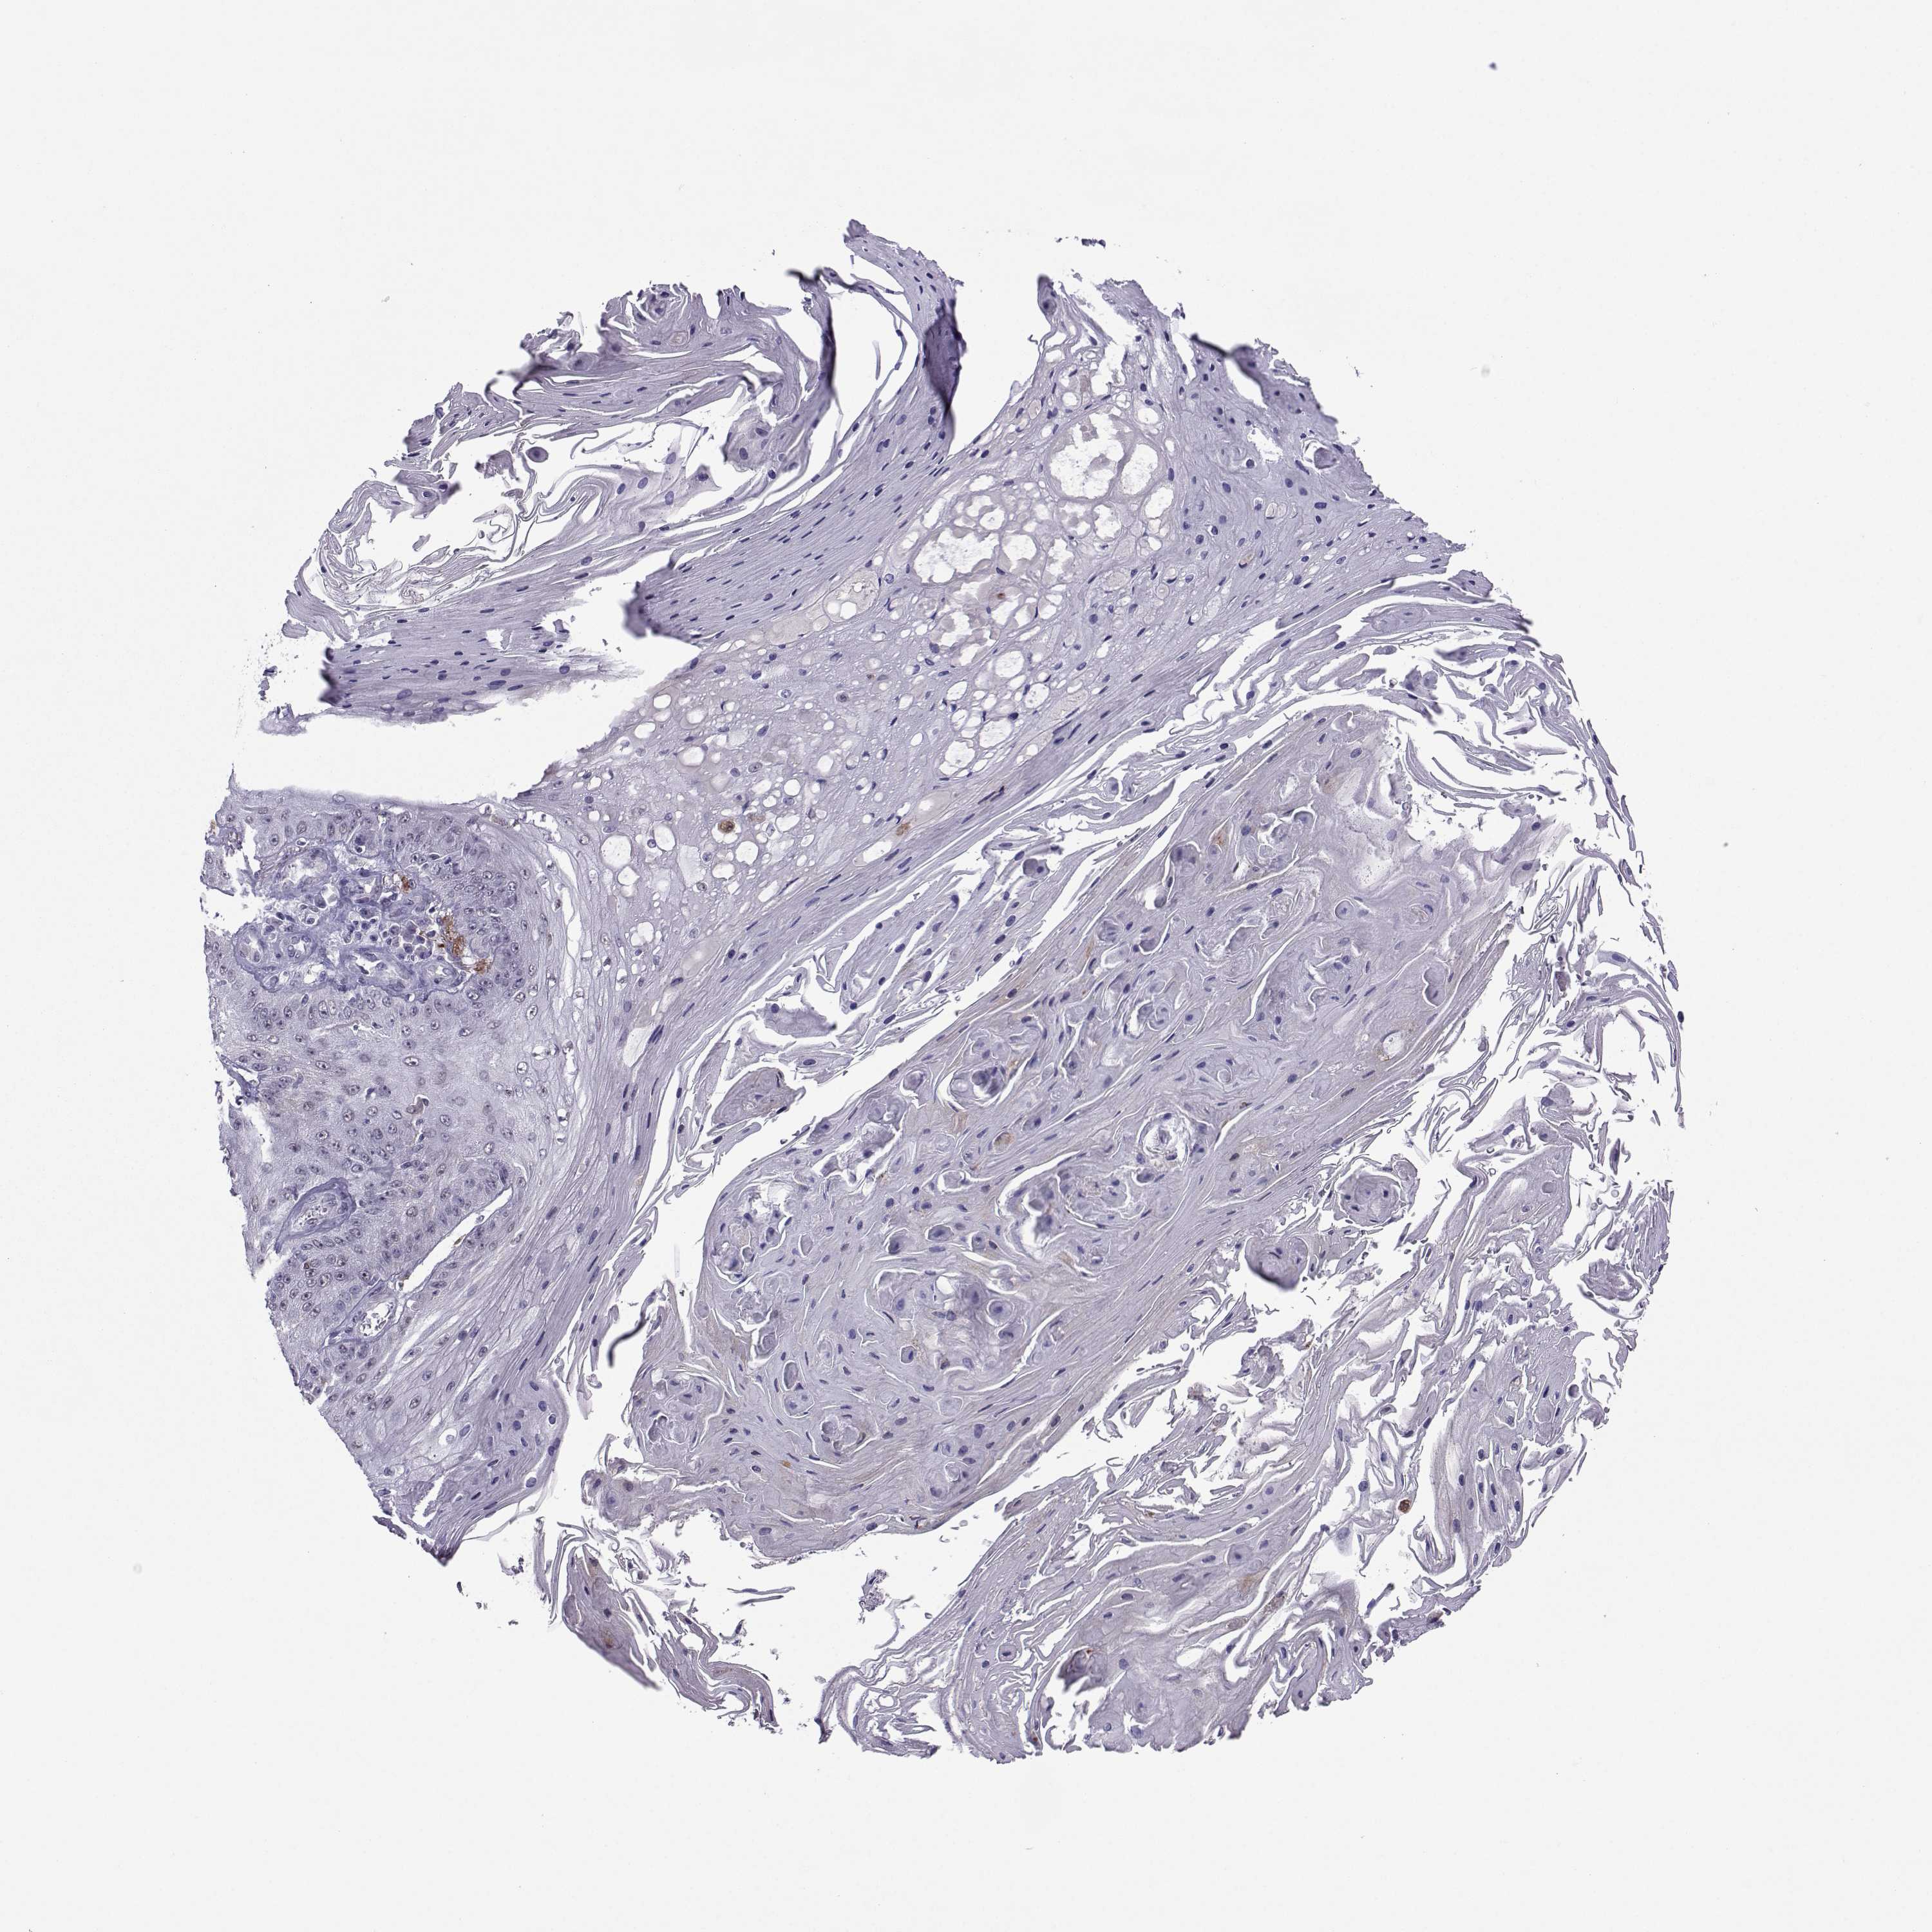

Basal cell and squamous cell cancer

SKIN CANCER - Protein expressioni

A mouse-over function shows sample information and annotation data. Click on an image to view it in a full screen mode. Samples can be filtered based on level of antibody staining by selecting one or several of the following categories: high, medium, low and not detected. The assay and annotation is described here.

Antibody stainingi

Antibody staining in the annotated cell types in the current human tissue is reported as not detected, low, medium, or high, based on conventional immunohistochemistry profiling in selected tissues. This score is based on the combination of the staining intensity and fraction of stained cells.

Each image is clickable and will lead to virtual microscopy that enables deeper exploration of all samples and also displays staining intensity scores, fraction scores and subcellular localization as well as patient and tissue information for each sample.

Antibody HPA005516

Antibody CAB015427

Basal cell carcinoma

Squamous cell carcinoma, NOS